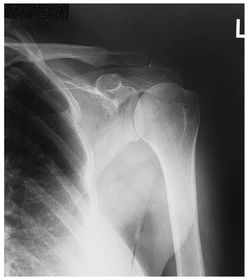

Which projections/positions are these? (top->bottom) TOP: Scapular Y-View _________________________ BOTTOM: AP External Rotation (greater tubercle in profile)